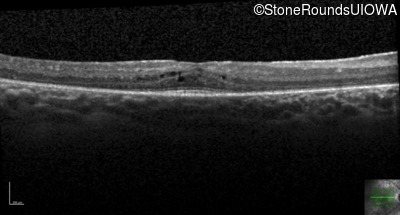

| Age at visit: 24 years |